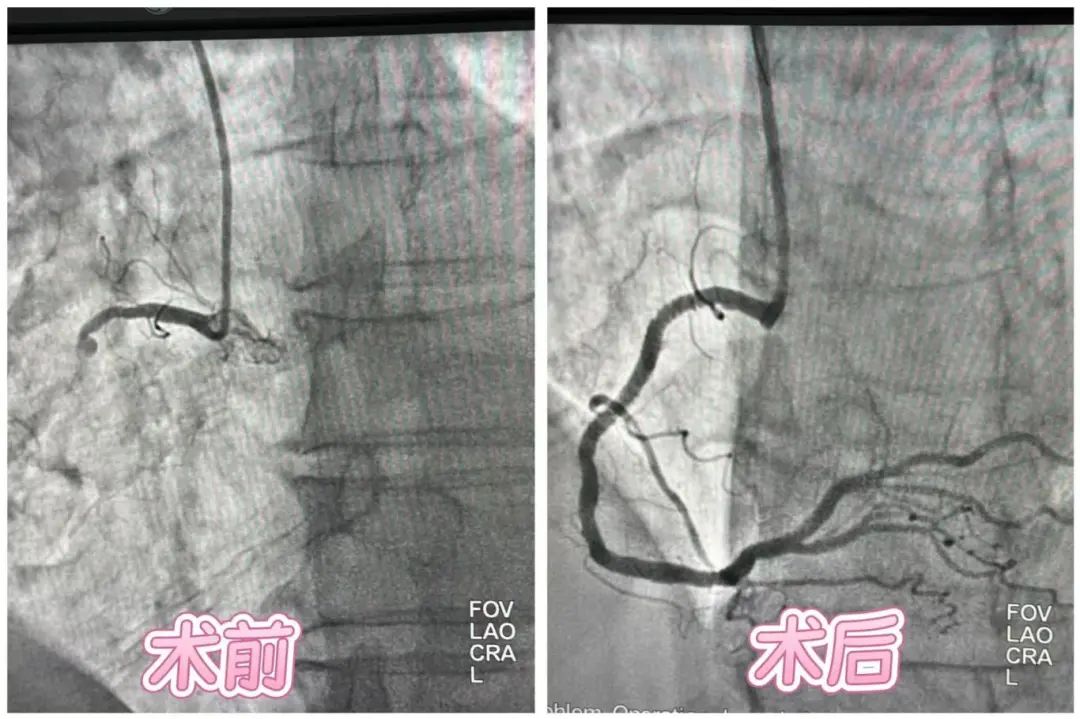

近日,铜仁市万山区人民医院接诊了一位79岁突发胸痛、大汗淋漓的男性患者。该患者入院后心电图提示急性下壁ST段抬高型心肌梗(STEMI),救治团队立即启动绿色通道,绕行CCU直达导管室,从首次医疗接触到导丝通过(FMC-to-Wire)仅97分钟(国际标准要求≤120分钟),通过球囊扩张、支架植入迅速恢复血流,最大限度保护了心肌功能。 从就诊到血管开通医护团队仅用38分钟便打赢这场“心脏保卫战”,展现了急性心梗救治的“速度与激情”!